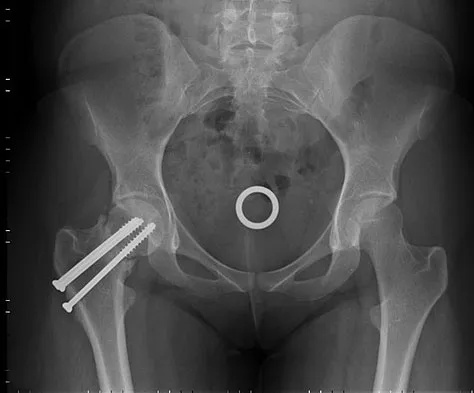

A 40 year-old-man was involved in a motor vehicle accident and sustained the pelvic injury seen in Figures 24a and 24b. Definitive management of the injury should consist of reduction by